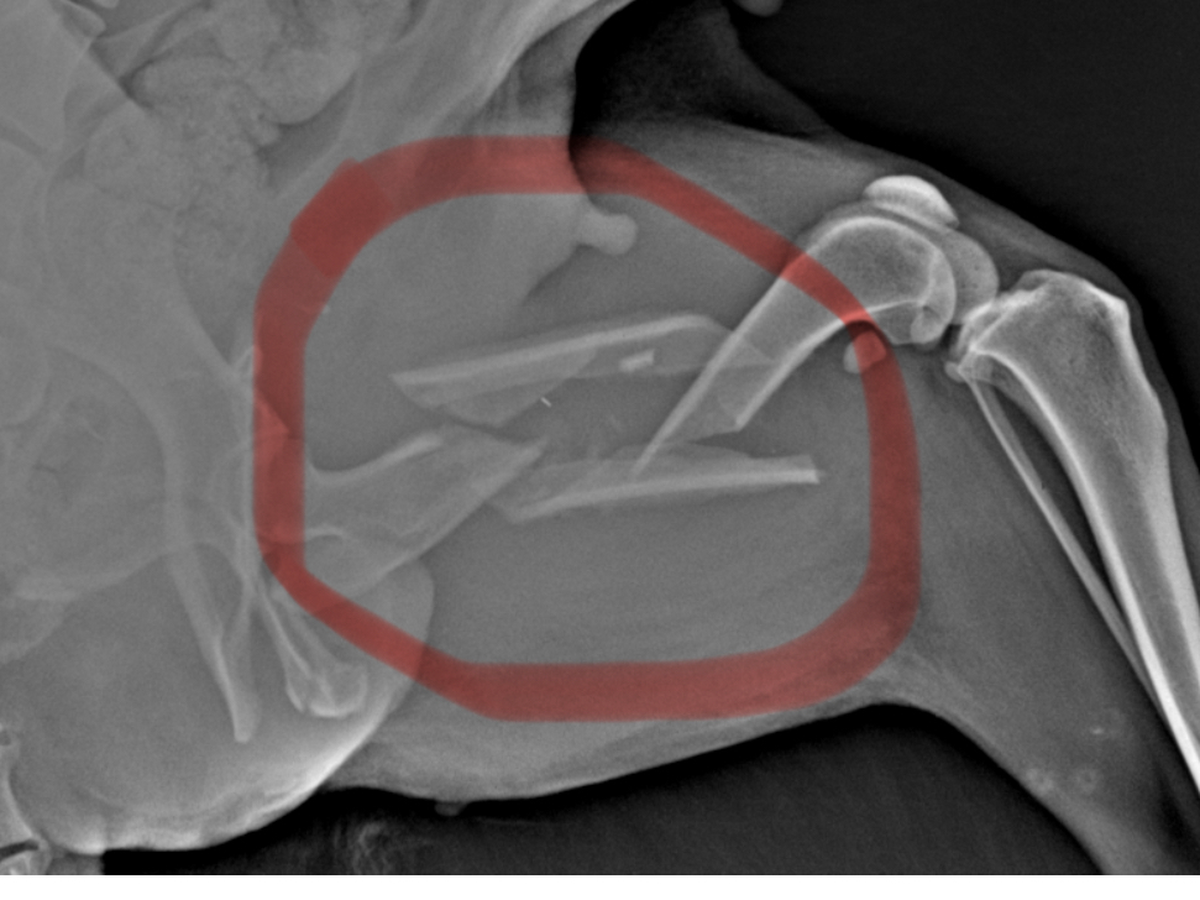

Hallo, ich bin Bianca und das ist Mina. Ich habe diese Hündin angefahren im Straßenrand gefunden, nach Untersuchung und Röntgen ein doppelter Bruch im Oberen Hinterbein.